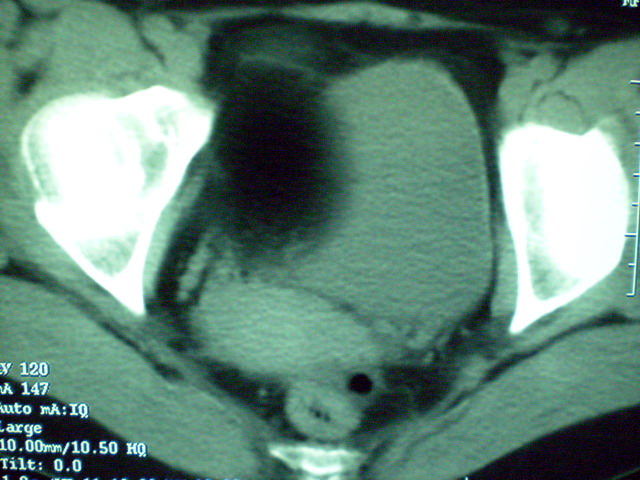

f 60y,b超提示脂肪瘤.[img][/img]

右侧附件囊性畸胎瘤,三种组织均见.

那个高密度灶形状好象牙齿。典型,收藏了

脂肪密度肿块,内可见团块状影,典型皮样囊肿

的确比较典型的畸胎瘤!不过,应该确切的说是盆腔畸胎瘤,右侧附件来源的可能性比较大。

有钙化,畸胎瘤